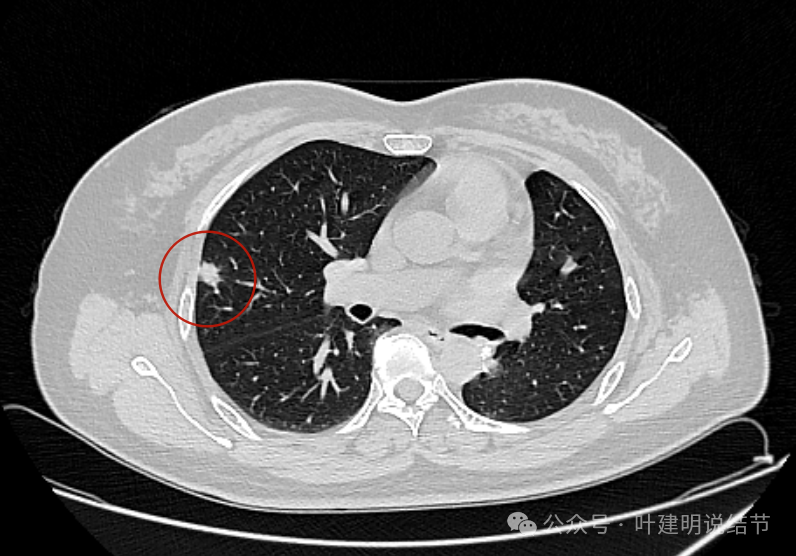

边缘不平,实性密度,贴着胸壁,胸壁处无明显增厚或胸膜反应。

表面不平,血管走向病灶。部分边缘较为平直。